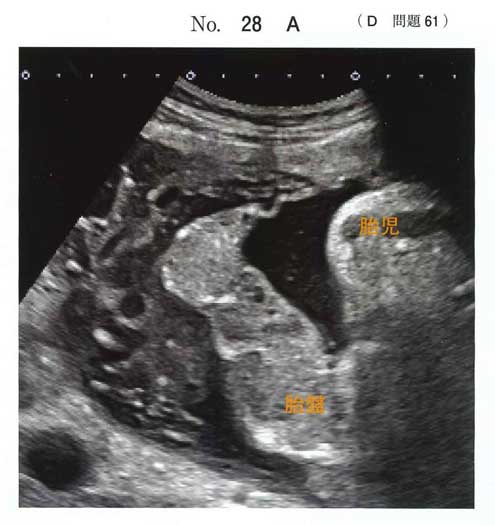

常位胎盤早期剥離。

超緊急帝王切開の適応で「直ちに」というのは帝王切開の方針を宣言してから30分以内、理想は15分以内に胎児を取り出すことです。

産科DICのリスクも高い疾患であり胎児を取り出した後は出血との戦いになることも踏まえて対応する必要があります。